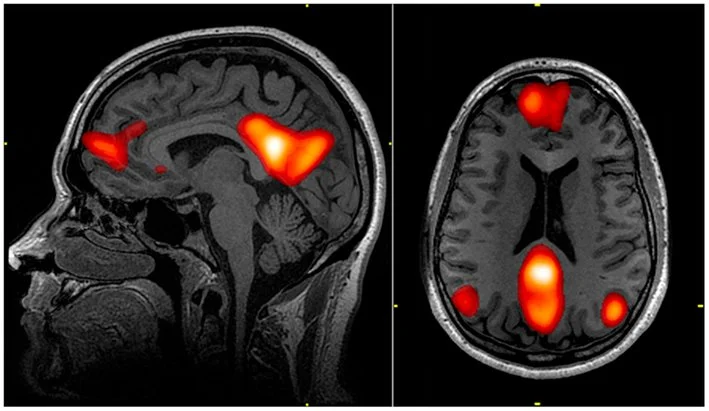

Ảnh chụp fMRI cho thấy các vùng thuộc mạng lưới mặc định (default mode network), bao gồm: vỏ não trước trán lưng-trung (dorsal medial prefrontal cortex), vỏ não đai sau (posterior cingulate cortex), thuỳ trước chêm (precuneus) và hồi góc (angular gyrus).

Nguồn: https://en.wikipedia.org/wiki/Default_mode_network

Mạng lưới thần kinh phân bố rộng khắp trong não có liên quan đến trầm cảm được gọi là mạng lưới chế độ mặc định (default mode network - DMN). Đúng như tên gọi, DMN hoạt động như một dạng “màn hình chờ” của não khi nó ở trạng thái nghỉ ngơi. DMN còn được gọi là “năng lượng tối của tâm trí” do xu hướng can thiệp vào các hoạt động não bộ có định hướng nhiệm vụ và tiêu tốn một lượng lớn tài nguyên chú ý hữu hạn của não (Raichle et al., 2001). Sự kích hoạt của mạng lưới này có liên quan đến nhiều hiện tượng tinh thần gắn liền với trầm cảm, bao gồm mơ màng, mất tập trung, giảm nhạy cảm với các tín hiệu cảm giác từ cơ thể và gia tăng khả năng hồi tưởng ký ức một cách tự do (Buckner, Andrews-Hanna & Schacter, 2008; Spreng et al., 2013).